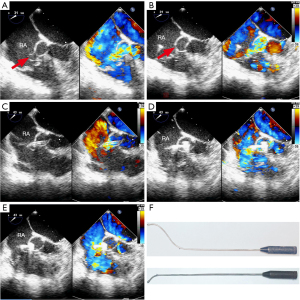

Three types of occlusion devices (Lifetech Scientific Co., Ltd., Shenzhen, China) were used in this study: (I) patent ductus arteriosus (PDA) occluder; (II) muscular VSD occluder; and (III) small-waist double disk VSD occluder (Figure 1).

A 4.0-cm parasternal incision was made in the fourth right interspaces when RSVA occurred in the RA. Superficial tissues were dissected bluntly to enter the pleural space. Exposure was optimized with a mini-incision retractor. The pericardium was incised and cradled. Two purse-string sutures of 4-0 polypropylene (Ethicon, Somerville, NJ, USA) were placed on the RA after systemic anticoagulation with heparin (1.0 mg/kg). A right atrial puncture was performed within the purse-string sutures, and then the hollow probe was inserted immediately. First, the hollow probe-assisted delivery system was placed into the ascending aorta (AO) through the rupture opening. A flexible 0.035-inch guidewire was introduced into the AO through the hollow probe, and then the hollow probe was removed. Second, the delivery sheath was sent into the AO along the guidewire, and then the guidewire was pulled out. The occluder prepared in advance was implanted along the sheath. The first disc was opened in the AO and pulled back to the anchor at the rupture site, and another disc was opened next. When the shunt disappeared, the rest of the device was deployed immediately (Figure 2). Aortic valve regurgitation and the presence of a residual shunt were excluded before detaching the device. Device stability was ascertained by a push-pull maneuver and released when the assessment was satisfactory. The whole operation process was guided and monitored under TEE. After removing the device from the delivery cable, TEE was repeated to assess the position of the occluder, to identify any residual shunts, and to evaluate aortic valve function.